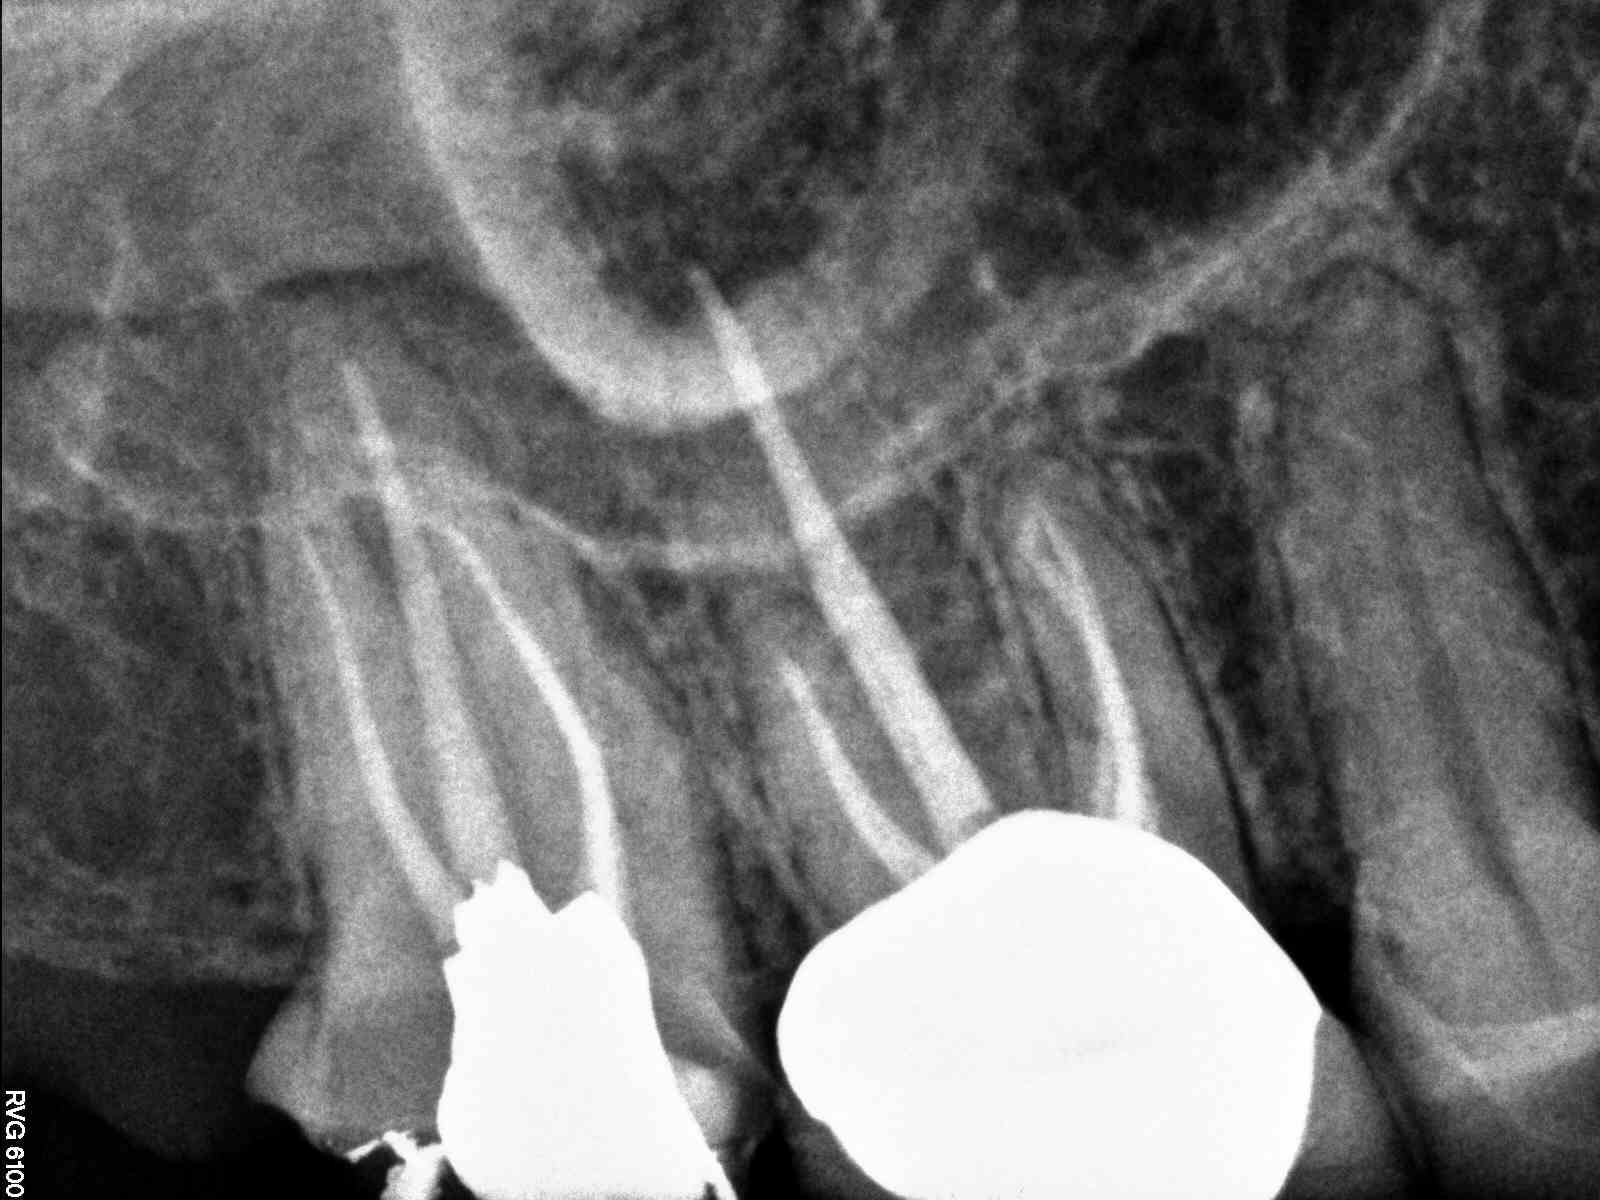

| Did #3 a year or so prior looks good. |